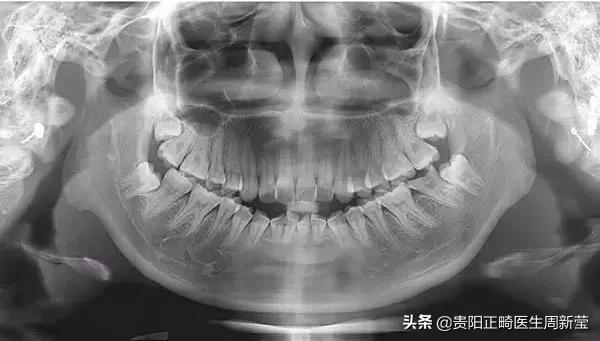

2、牙齿可分为切牙、尖牙、双尖牙和磨牙4种。每个牙齿均由露在牙槽骨外的牙冠和长在牙槽骨内的牙根,以及牙冠、牙根之间的牙颈组成。